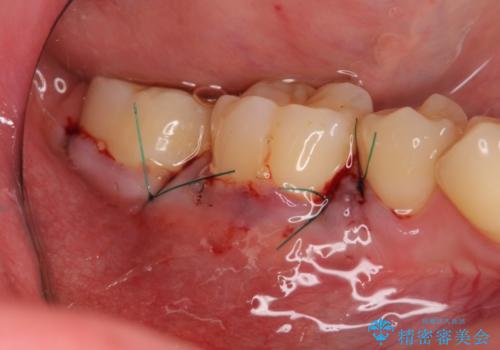

写真ではわずかな差ですが、移植後は知覚過敏の症状が全くなくなり歯ぐきの厚みも獲得できたことから安定して歯ブラシが行えるようになったと満足いただくことができました。